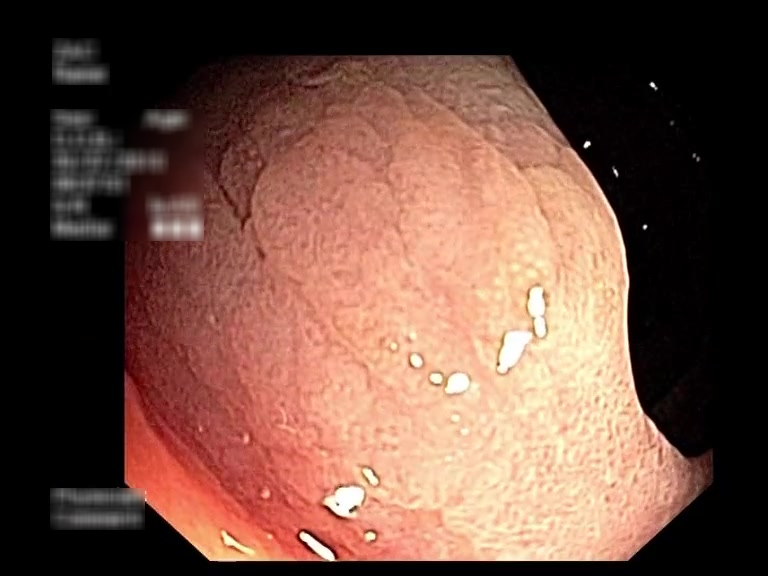

| Lesion | White Light Frame | NBI Frame | White Light Video | NBI Video | Camera Calibration |

| serrated_01 |  |

|

WL.mp4 | NBI.mp4 | cam.xml |